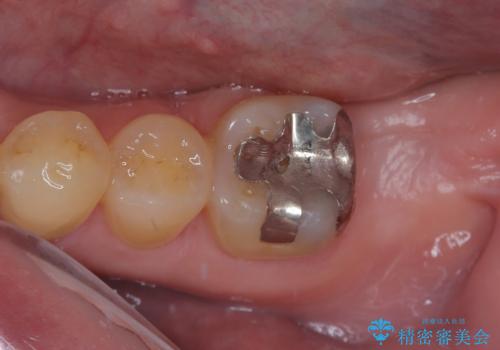

- 奥歯のむし歯治療を希望して来院された患者様です。

上顎の奥歯は、左右ともに外側に転位しており、特に右上はむし歯の範囲が広く、根管治療も必要な状態でした。

上顎左右の歯をアンカースクリューを用いた部分矯正により位置を修正し、オールセラミッククラウンにて補綴治療を行うこととしました。